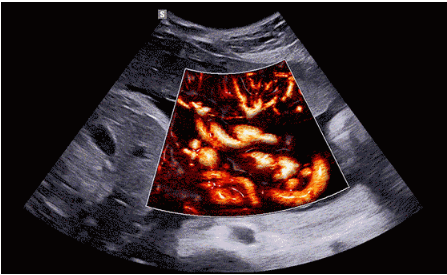

人性化設(shè)計(jì)的極致表現(xiàn),三星推出全新母嬰超聲系統(tǒng)——Hera i 10

近日三星醫(yī)療推出了一款全新的母嬰超聲系統(tǒng)——Hera i 10。該款產(chǎn)品除了成像能力本身,人性化的座椅設(shè)計(jì),探頭擺放位置等也是亮點(diǎn)之一。

Hera i 10繼承并升級(jí)了全球首款5D超聲“三星麥迪遜WS80A”的“晶體結(jié)構(gòu)”成像理念,即將CrystalBeam?波束形成技術(shù)、CrystalLive?超聲成像引擎、S-Vue Transducer?視覺傳感器集于一身,提供更清晰的圖像。

CrystalBeam?是一種新的波束形成技術(shù),利用任意波形傳輸、大規(guī)模并行波束形成和合成孔徑技術(shù),產(chǎn)生更快的幀速率和更好的圖像均勻性。

CrystalLive?是三星最新的超聲成像引擎,同時(shí)增強(qiáng)了2D圖像處理能力、3D渲染能力和彩色信號(hào)處理能力,能夠在復(fù)雜情況下提供出色的圖像性能,具備檢測(cè)外周血管、微循環(huán)血流的能力。

2D成像方面,Hera i10集成了包括ShadowHDR?、HQ-Vision?、ClearVision等多項(xiàng)具有三星“血統(tǒng)”的技術(shù),加強(qiáng)了圖像的陰影抑制、減少偽影、緩和模糊區(qū)。

3D/4D成像方面,Hera i 10通過結(jié)合先進(jìn)的圖像渲染技術(shù),著重加強(qiáng)了邊緣和小結(jié)構(gòu)的可視化能力。

Hera i 10明顯區(qū)別于其他同類設(shè)備的亮點(diǎn)是安裝于顯示器右側(cè)的可調(diào)節(jié)座椅,最大尺寸長(zhǎng)度為7.5英尺(230厘米)x寬6英尺(183厘米)x高度5.7英尺(175厘米)。座椅可通過機(jī)械控制,自動(dòng)調(diào)整角度來配合醫(yī)生檢查和優(yōu)化患者就診體驗(yàn)。

顯示器角度可手動(dòng)調(diào)節(jié),座椅右側(cè)是一個(gè)同樣可移動(dòng)的探頭支架,方便醫(yī)生操作。

4溫馨舒適的就診環(huán)境

處于孕期的女性因?yàn)榧に刈兓托睦碓?,往往比平時(shí)更敏感。傳統(tǒng)母嬰超聲檢查需要受檢孕婦躺在冰冷的檢查床上并頻繁的擺出不同檢查體位,很容易造成就診者的緊張感,降低就診體驗(yàn)。而Hera i 10很好的洞察到了這種問題,設(shè)計(jì)的檢查椅不僅可以方便醫(yī)生擺位、操作,更兼優(yōu)秀的顏值,可以為就診者提供比傳統(tǒng)超聲檢查室更加溫馨舒適的就診環(huán)境。